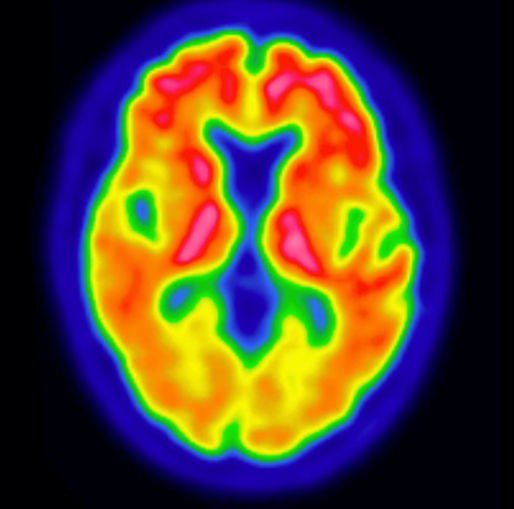

VIZAMYL™ (flutemetamol F 18 injection) is indicated for positron-emission tomography (PET) of the brain to estimate amyloid beta neuritic plaque density in adults with cognitive impairment for:

- Risk of Image Misinterpretation and Other Errors: Errors may occur in the estimation of amyloid beta neuritic plaque density during VIZAMYL image interpretation. The use of clinical information in the interpretation of VIZAMYL images has not been evaluation and may lead to an inaccurate assessment. Extensive brain atrophy and motion artifacts that distort the image may limit the ability to distinguish gray and white matter on a VIZAMYL scan. Perform image interpretation independently of the patient’s clinical information. For cases where there is uncertainty as to the location of cortical signal, use co-registered anatomical imaging to improve localization of signal or examine the striatum for VIZAMYL signal as it is less affected by atrophy.